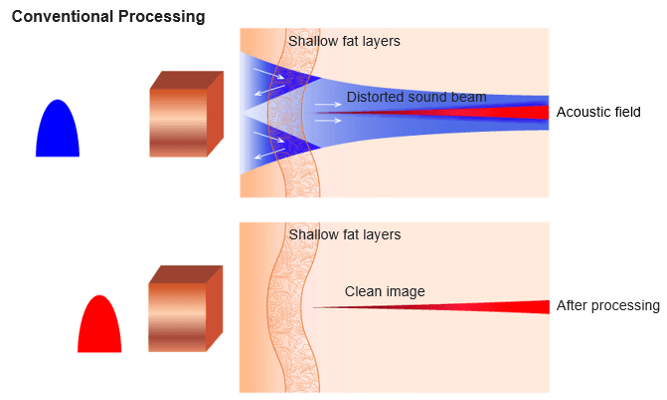

Tissue Aberrations

Harmonic imaging is also used for aberration corrections. Aberration phenomenon occurs when the ultrasonic waves are distorted due to local changes in the speed of sound. Shallow fat and skin layers distort sound beam. It is important to know that distortions are of low energy but send sound in random directions.

As aberrations are also of low energy, they never develop harmonics. Therefore receiver filters tuned at harmonic frequency remove aberrations at f0 and clean up the image.